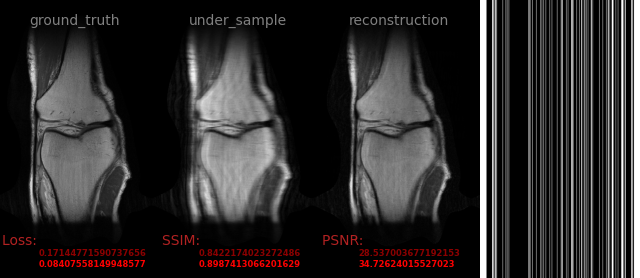

AVS-Net

Image-to-Image

medical

avs_b5